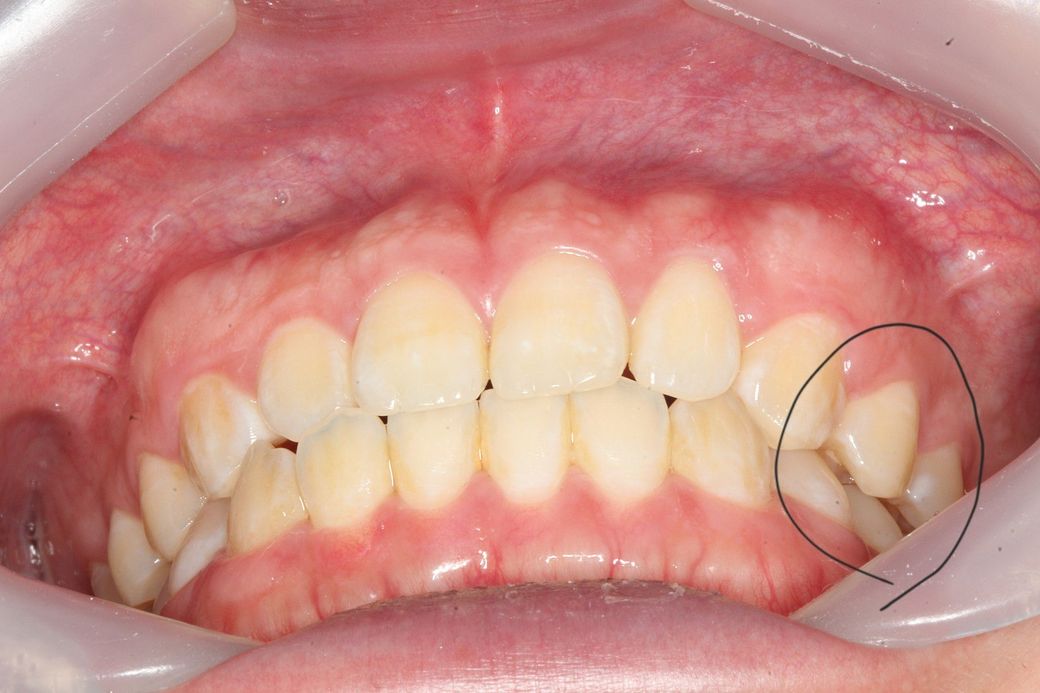

턱이 왼쪽으로 canting 되어있어도 어금니 교합이 맞을수 있나요?

턱이 왼쪽으로 비대칭이 약간 있는데 그래도 어금니 교합이 맞을수있나요?

주관적인 생각으로 약간 아랫뼈? 치아?들이 전체적으로 왼쪽으로 이동한 느낌인데 이러면 어금니 교합도 틀어지지않나요?

사진상 왼쪽어금니들은 윗아래 옆면 딱붙는 느낌이면

오른쪽은 옆면이 공간이 남는 느낌? 입니다

• 1번 째 사진